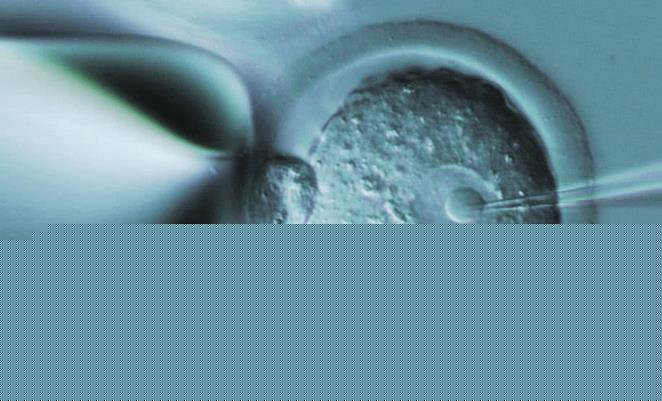

试管婴儿胚胎移植后生化与不着床哪个情况好?

试管婴儿的生化与不着床都代表着试管婴儿的失败意思,并不会存在哪个情况好哪个情况不好之分。事实上,所谓的生化,其实指的是怀孕初期,也就是怀孕前三个月,胚胎已经着床,但发育成胚芽后就不再发育了。一般导致这种情况的原因非常多。不着床主要是指胚胎着床期间没有成功着床,即未怀孕,在胚胎移植至子宫腔内未发育,直接走向凋亡。

生化妊娠是指发生在妊娠5周内的早期流产,特点是HCG阳性(25mIU/mL),超声检查看不到孕囊。生化妊娠与胚胎停育对患者来说,都属于一次失败的妊娠,但他们并不是一回事。

生化妊娠大致可以理解为精子和卵子受精了,迈出了孕育生命的第一步。因为受精卵着床后第6天即开始产生少量的HCG,一般排卵后8天可以从外周血中测出相应数值。但这时的HCG(+)的数值是没有临床意义的。这时测出的妊娠,无法判别妊娠的部位、也无法预知它的前途。